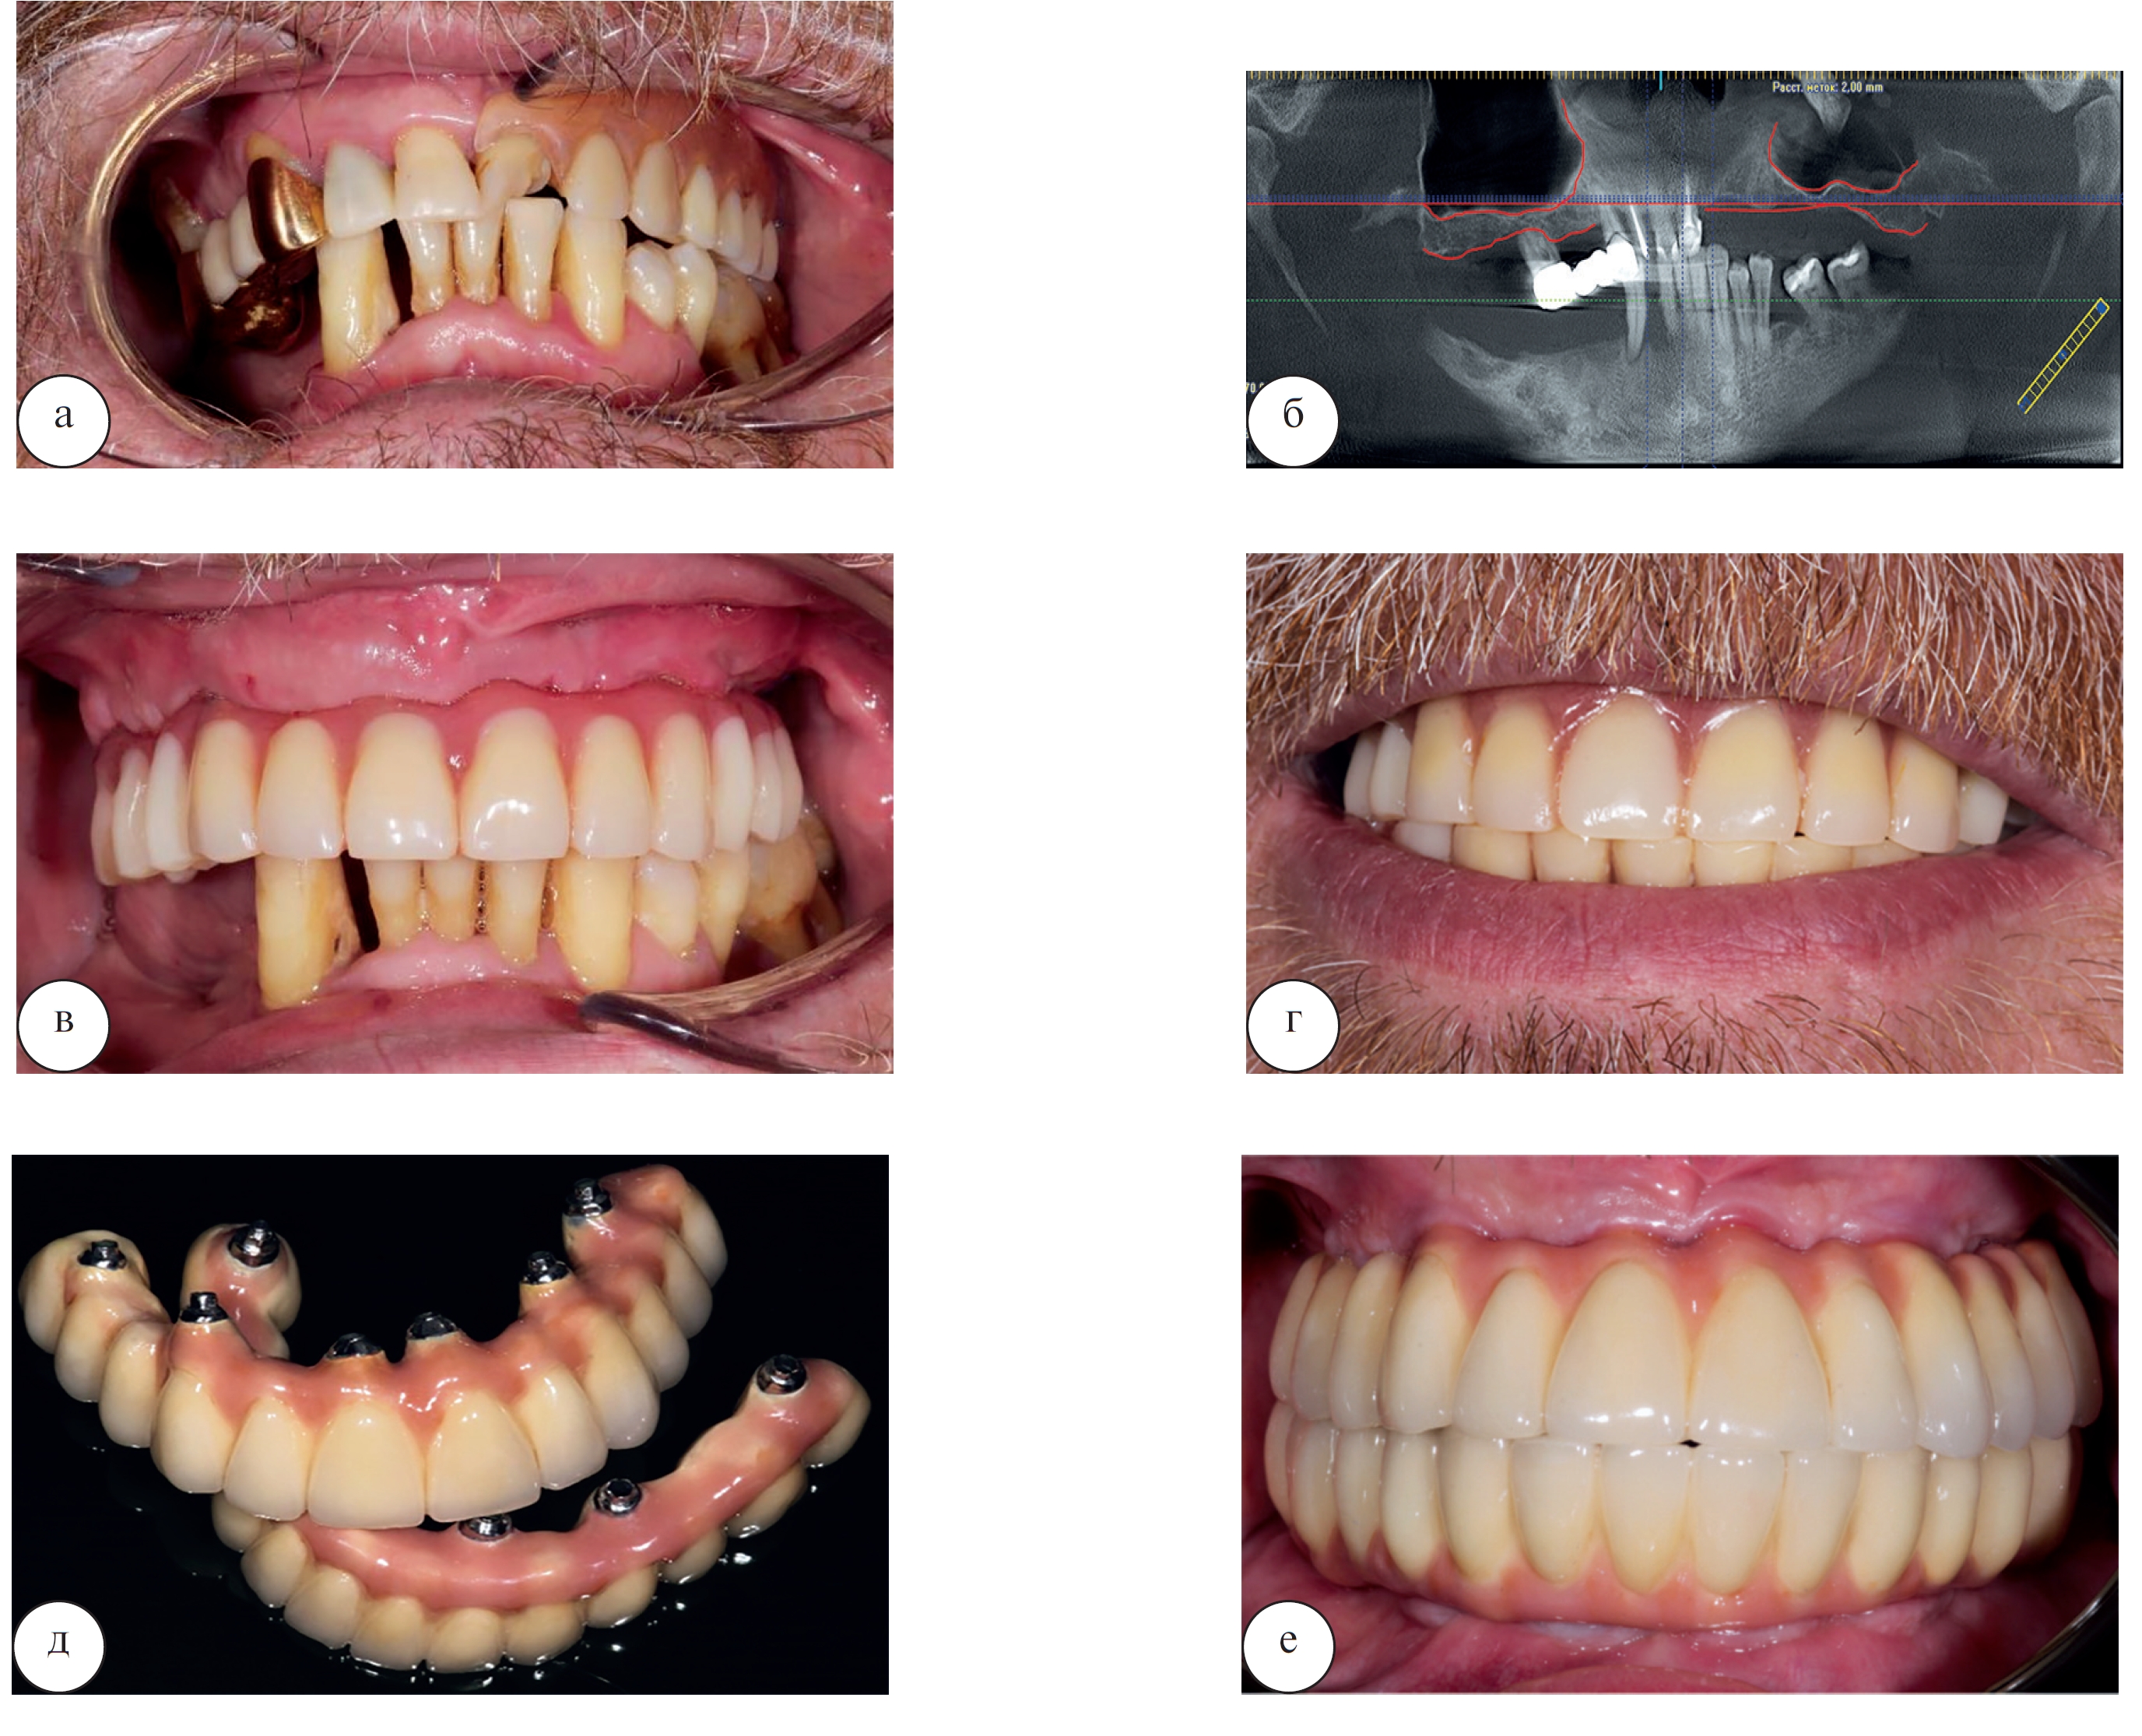

Для реализации этого протокола установка имплантатов осуществляется во фронтальном отделе челюстей, где атрофия костной ткани идет не такими быстрыми темпами. Два имплантата в области резцов устанавливаются параллельно, еще 2 – в боковых отделах челюсти (обычно в проекции премоляров) под углом для правильного распределения жевательной нагрузки. Клинический пример стоматологической реабилитации пациентки Ж. 49 лет с использованием четырех дентальных имплантатов представлен на рисунке 10.

Применение методики на 4 дентальных имплантатах позволяет также выполнить установку временной ортопедической конструкции сразу после проведения операции или в течение 3 дней после нее.

Рис. 10. Стоматологическая реабилитация с использованием протокола на 4 дентальных имплантатах у пациентки Ж. 49 лет: а – исходная клиническая картина в полости рта; б – клиническая картина в полости рта после удаления всех съемных конструкций; в – временный условно-съемный акриловый протез установлен по методике немедленной нагрузки; г – улыбка пациента с временными акриловыми протезами на верхней и нижней челюсти; д – вид слизистой в полости рта на контрольном осмотре через год после операции; е – срез компьютерной томограммы через год после операции